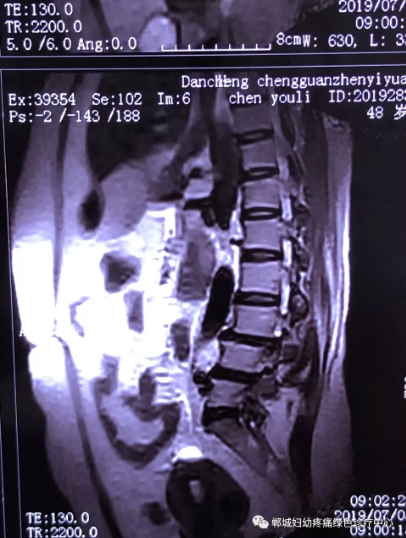

2年前,雙樓鄉(xiāng)的陳女士不小心摔了一跤后出現(xiàn)腰痛,當(dāng)時(shí)到藥店買了膏藥來(lái)貼,疼痛減輕了一些,但是從此以后反反復(fù)復(fù)出現(xiàn)腰痛。到處進(jìn)行治療,不見(jiàn)好轉(zhuǎn),最近腰痛加重了,痛得受不了,出現(xiàn)行走后甚至持續(xù)的雙下肢后側(cè)或后外側(cè)放射性的疼痛麻木、間歇性跛行等癥狀。陳女士趕忙去醫(yī)院治療,做了磁共振檢查后確診為腰椎滑脫、腰椎反弓。醫(yī)生都告訴她需要手術(shù)治療。隨后她又帶著片子咨詢了好幾家醫(yī)院,結(jié)果都是一樣,她已經(jīng)做好了手術(shù)的打算。

治療前

不經(jīng)意間聽(tīng)到有人說(shuō)醫(yī)院疼痛科可以不吃藥不打針,用無(wú)痛苦、無(wú)創(chuàng)傷的方法治療腰痛。陳女士就抱著試試看的心理來(lái)到了鄲城縣婦幼保健院疼痛科,疼痛科時(shí)慶祥主任詳細(xì)了解病情,結(jié)合腰椎磁共振及體征后告訴陳女士她不用手術(shù),通過(guò)腰椎脊柱定位周期減壓牽引系統(tǒng)(外星艙)也能解決腰痛、腰椎滑脫、腰椎反弓這些問(wèn)題。陳女士未曾想到經(jīng)過(guò)十五天的治療后腰部及下肢放射性疼痛癥狀基本消失。陳女士感到十分激動(dòng)與感謝,就在當(dāng)?shù)匦l(wèi)生院做了一個(gè)腰椎正側(cè)位x片和之前的片子作對(duì)比,發(fā)現(xiàn)腰椎滑脫明顯改善。她說(shuō)道:感謝鄲城縣婦幼保健院疼痛科的所有醫(yī)護(hù)人員、感謝外星艙脊柱減壓治好了我的腰痛,也感謝告訴我來(lái)這里的人,她的一句話,讓我省了好幾萬(wàn)元的手術(shù)費(fèi)!